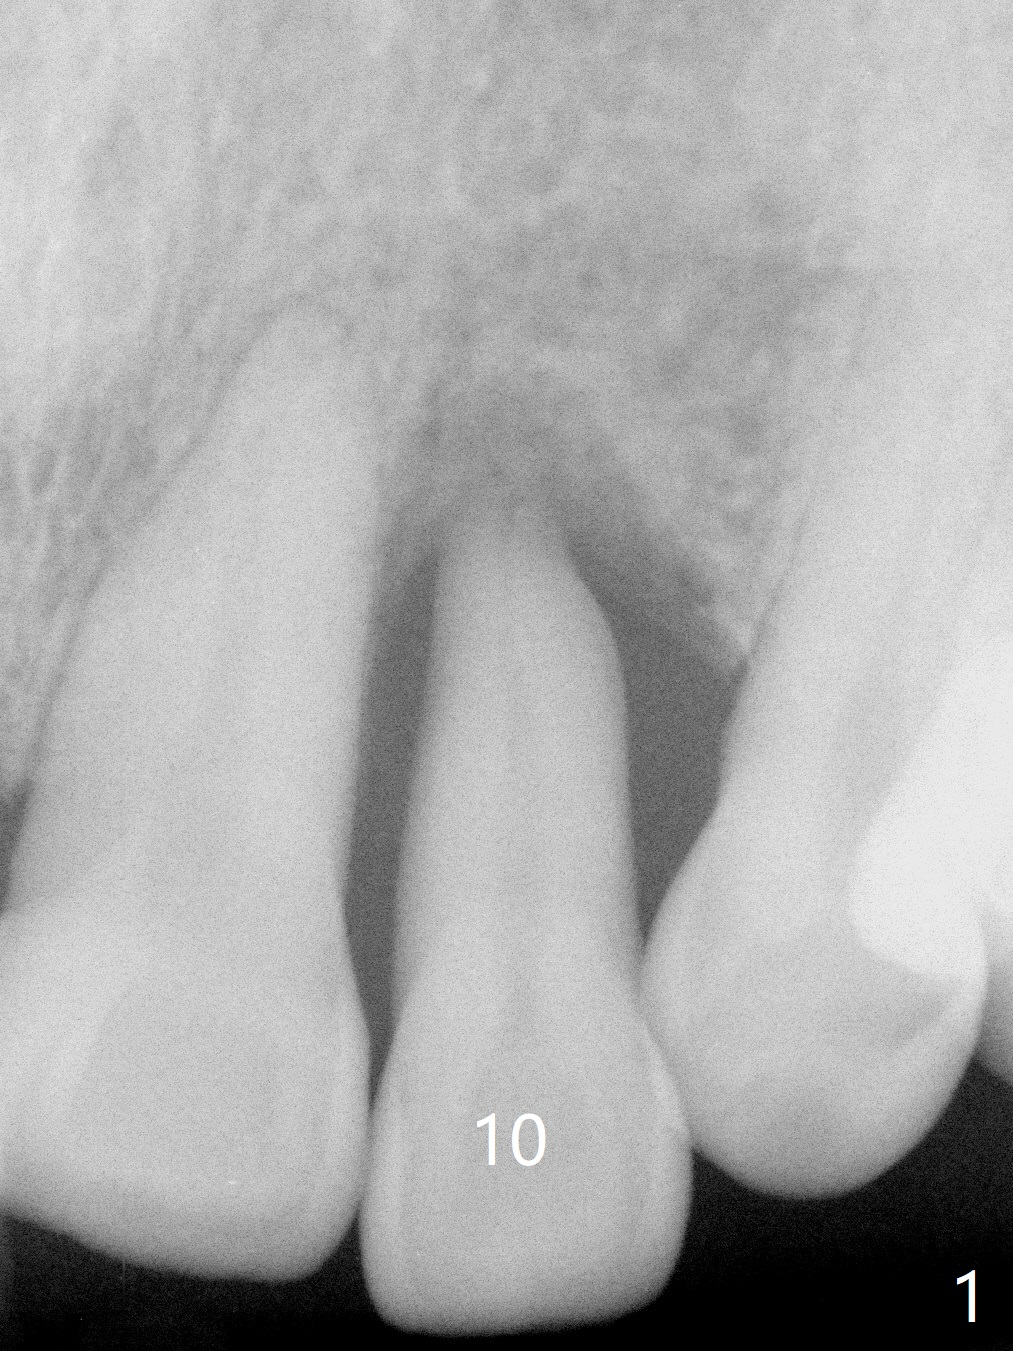

A 61-year-old man has chronic periodontitis and bruxism (Fig.1). Immediately after extraction and Clindamycin socket treatment, osteotomy is initiated with a 2 mm pilot drill at 20 mm in the lower 1/3 of palatal wall with normal saline irrigation, followed by 2.5-4 mm reamers at 20 mm (bone saved, Type III bone). A screw Implant (4.5x20 mm) is placed (45-50 Ncm, Fig.2). The root measurements were B-L 6.5 mm and M-D 5 mm. Autogenous bone is mixed SynthoGraft (size 50-500) ~ .3 g and blood. A 3.5x5 mm abutment is immediately cemented with an immediate provisional. There is positive bone growth 3 years post cementation (Fig.3 *). There is no buccal plate bone resorption 3 years 2 months post cementation (Fig.4 CT).